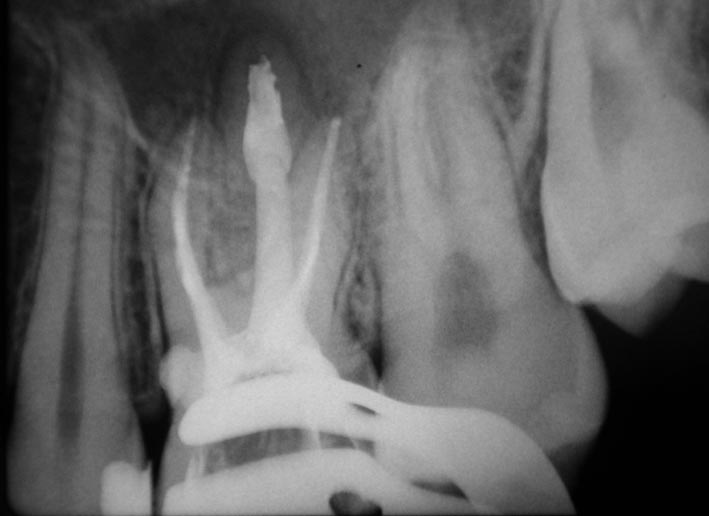

«L’imaging radiografico è fondamentale: dopo la raccolta dei dati anamnestici e un’accurata visita, il primo step è la radiografia periapicale eseguita con la tecnica dei raggi paralleli (centratori). Non sempre, tuttavia, questo esame consente di distinguere tra riassorbimento interno ed esterno; per questo è utile una seconda radiografia, con diversa inclinazione, che grazie alla sproiezione delle immagini può aiutare a chiarire il tipo di riassorbimento. Oggi però sappiamo che l’immagine bidimensionale presenta molti limiti; per questa ragione, le principali linee guida internazionali (AAE-American Association of Endodontists ed ESE-European Society of Endodontology) raccomandano un esame di secondo livello come la CBCT (FOV piccolo, alta risoluzione). Questo consente una diagnosi precisa, informazioni sulla reale estensione del processo distruttivo e, di conseguenza, un piano di trattamento più accurato».

Dal punto di vista biologico, i riassorbimenti derivano dall’attivazione di cellule clastiche capaci di degradare dentina e cemento, stimolate da fattori infiammatori o traumatici. «Le cause più comuni sono traumi, movimenti ortodontici, scaling e carie, ma talvolta il processo decorre del tutto senza sintomi. Clinicamente, i riassorbimenti radicolari possono restare occulti a lungo e venire diagnosticati solo con indagini radiografiche o, più recentemente, con CBCT, che ha migliorato la comprensione di localizzazione ed estensione del difetto, distinguendo chiaramente tra quadri interni ed esterni, distinzione fondamentale per strategie e prognosi».